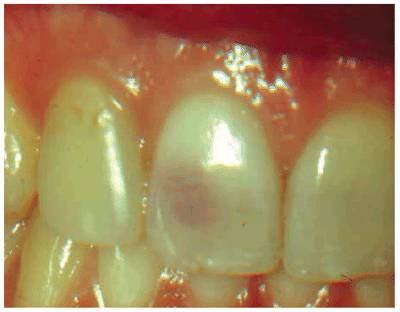

Transillumination via a fiber-optic light may be of great assistance in

detecting color shifts in a crown (Figures 19-1A, and 19-1B). A tooth with a pink or reddish

hue would more than likely indicate internal hemorrhage from a recent injury (Figure 19-2), a dental procedure (Figure 19-3), or gingival tissue hyperplasia

Figure 19-1A: Transillumination of a maxillary left central incisor with a necrotic pulp.

Figure 19-1B: Transillumination of the adjacent tooth with a vital pulp. Because there is active blood flow through the live pulp tissue, the tooth appears brighter to the fiber-optic light than the adjacent tooth with a necrotic pulp.

Figure 19-4A: Pink spot as a result of external resorption.

Figure 19-4B: Radiograph of the same tooth showing external resorption.

Figure 19-4C: Pink spot as a result of internal resorption.

Figure 19-4D: Radiograph of the same tooth showing internal resorption.